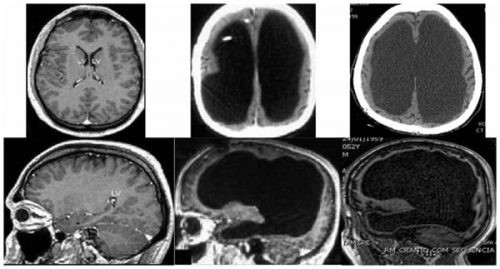

3. Chết là chết não?

Theo các tiêu chuẩn mới dựa trên các tiến bộ về y sinh thì một con người được coi là chết khi hoạt động của toàn bộ não bộ bị ngừng hoạt động không hồi phục. Trên thực tế lâm sàng thì hiện tượng chết não thường do hai nguyên nhân chính: Thứ nhất là những chấn thương hay xuất huyết nặng của não bộ, nguyên nhân này ít gặp.

Trong khi đó nguyên nhân do sự ngừng đập của tim làm gián đoạn cung cấp máu cho não, dẫn đến thếu máu não trầm trọng và kết quả là chết não hoàn toàn là nguyên nhân hay gặp hơn cả, trong rất nhiều bệnh và nhiều trường hợp ngừng đập của tim.

Khi bệnh nhân được thở máy hoặc gắn máy tạo nhịp tim để duy trì sự hoạt động của phổi và tim thìphải cần đến tiêu chuẩn chết não để chẩn đoán một cách chắc chắn là bệnh nhân đã tử vong. Việc chẩn đoán chết não rất đơn giản với sự trợ giúp của máy đo điện não, khi không thấy sự xuất hiện của các sóng đặc trưng cho hoạt động của não bộ là sóng alpha, béta hay delta mà chỉ là một đường đẳng điện trong suốt quá trình đo.

Não có vai trò rất quan trọng trong duy trì sự thống nhất của hệ thần kinh và mô não là mô nhậy cảm nhất khi bị thiếu oxy. Trong thực tế, chỉ cần thiếu oxy khoảng 5 phút là mô não bị chết vĩnh viễn không có khả năng hồi phục. Do đó cho dù bệnh nhân có chết vì ngừng thở hay ngừng tim trước đó cũng kéo theo sự chết của các tế bào não. Trong một số trường hợp thì dù não đã chết. nhưng tim và phổi vẫn hoạt động, vẫn cung cấp máu cho các cơ quan như: thận, gan, giác mạc... thì việc sử dụng những cơ quan này để ghép theo kinh điển là rất tốt.